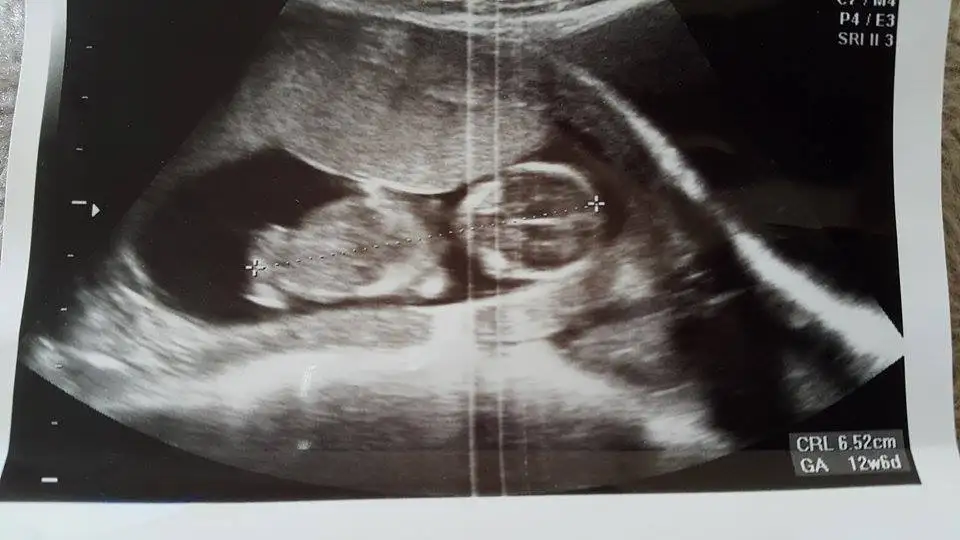

13+4üm hanımlar bugün çekildi banada yorum yapabilir misiniz?

Canım benim uzun zamandır girmiyordum ilk kez gördüm çok mutlu oldum Allah tamamına erdirsinKizlarrr mujdeler olsummm cinaiyeyimiz belli oldu :))) kesinlestii sonunda gosyerdiiii .... kizimisss ... sabahat melek azraa :))

doktorda kıza benzetmişti biri daha kız dedi şimdi hayırlısı olsun :)Kız bence:)